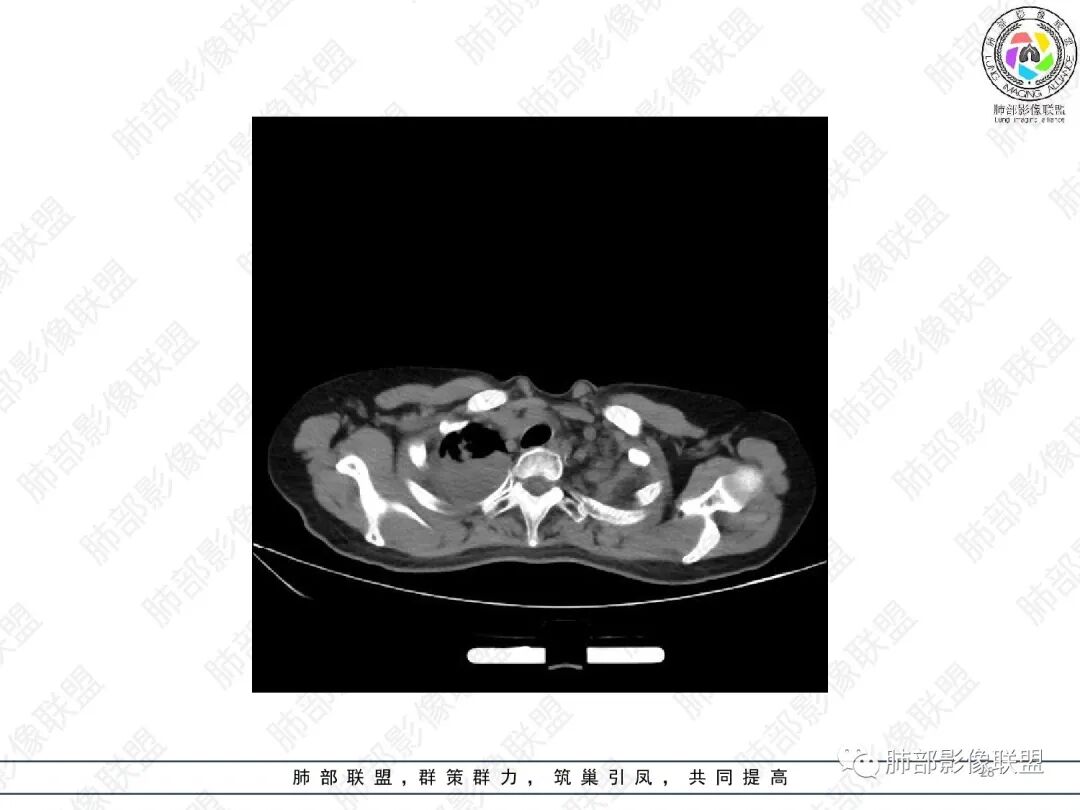

1.中年女性,主因“咳嗽、咳痰半年余”入院,既往史:8年前因左肺病在外院变行左肺叶切除术,诉术后抗结核治疗1年,具体病理等不详。实验室IGE显著增高。

女,51,咳嗽、咳痰半年。左下叶手术史,术后抗TB治疗史。胸部CT:右肺上叶尖段团片影,边界较清,部分层面周围清楚GGO;形态不规则,近端呈指套样改变;密度不均,内见斑点状高密度灶;胸膜牵拉。右肺中叶内侧段斑片实变影,邻近多发小树芽影?左侧胸廓塌陷,左上叶多发小结节影,支气管扩张样改变,左上叶支气管腔可见钙化影。考虑TB,鉴别ABPA、腺Ca等。